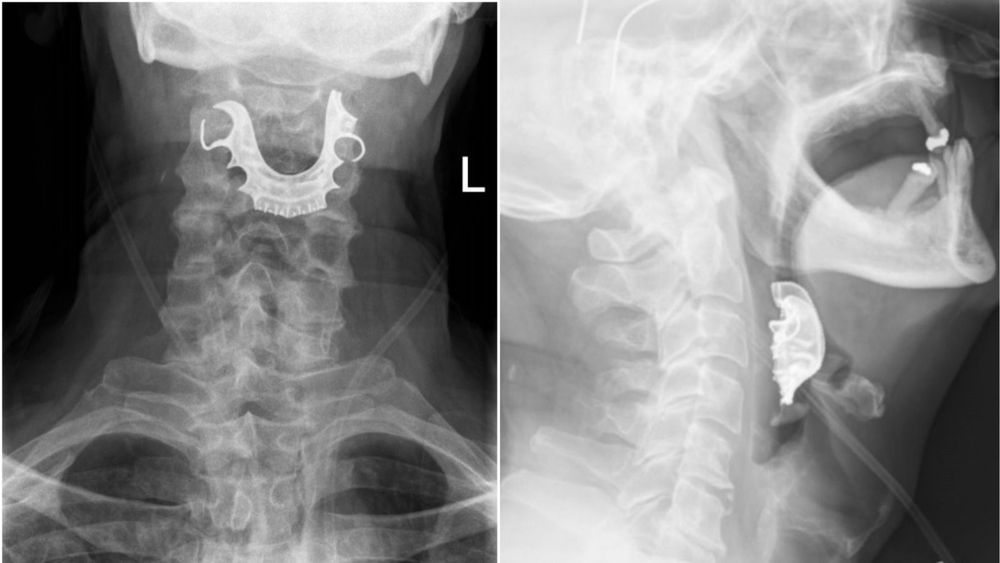

सरळ मुद्द्याला हात घालूया. त्याचं झालं असं, की युकेच्या एका ७२ वर्षांच्या आजोबांवर पोटाची शस्त्रक्रिया करण्यात आली होती. शस्त्रक्रियेच्या ६ दिवसानंतर हे आजोबा पुन्हा हॉस्पिटलमध्ये आले, तेव्हा त्यांच्या घशातून रक्त निघत होतं. त्यांचा घसा दुखत होता, अन्न गिळता येत नव्हतं आणि खोकल्यासोबत रक्त येत होतं. त्यांनी डॉक्टरांना म्हटलं की ऑपरेशन झाल्यापासून त्यांना अन्न गिळता येत नाहीय.